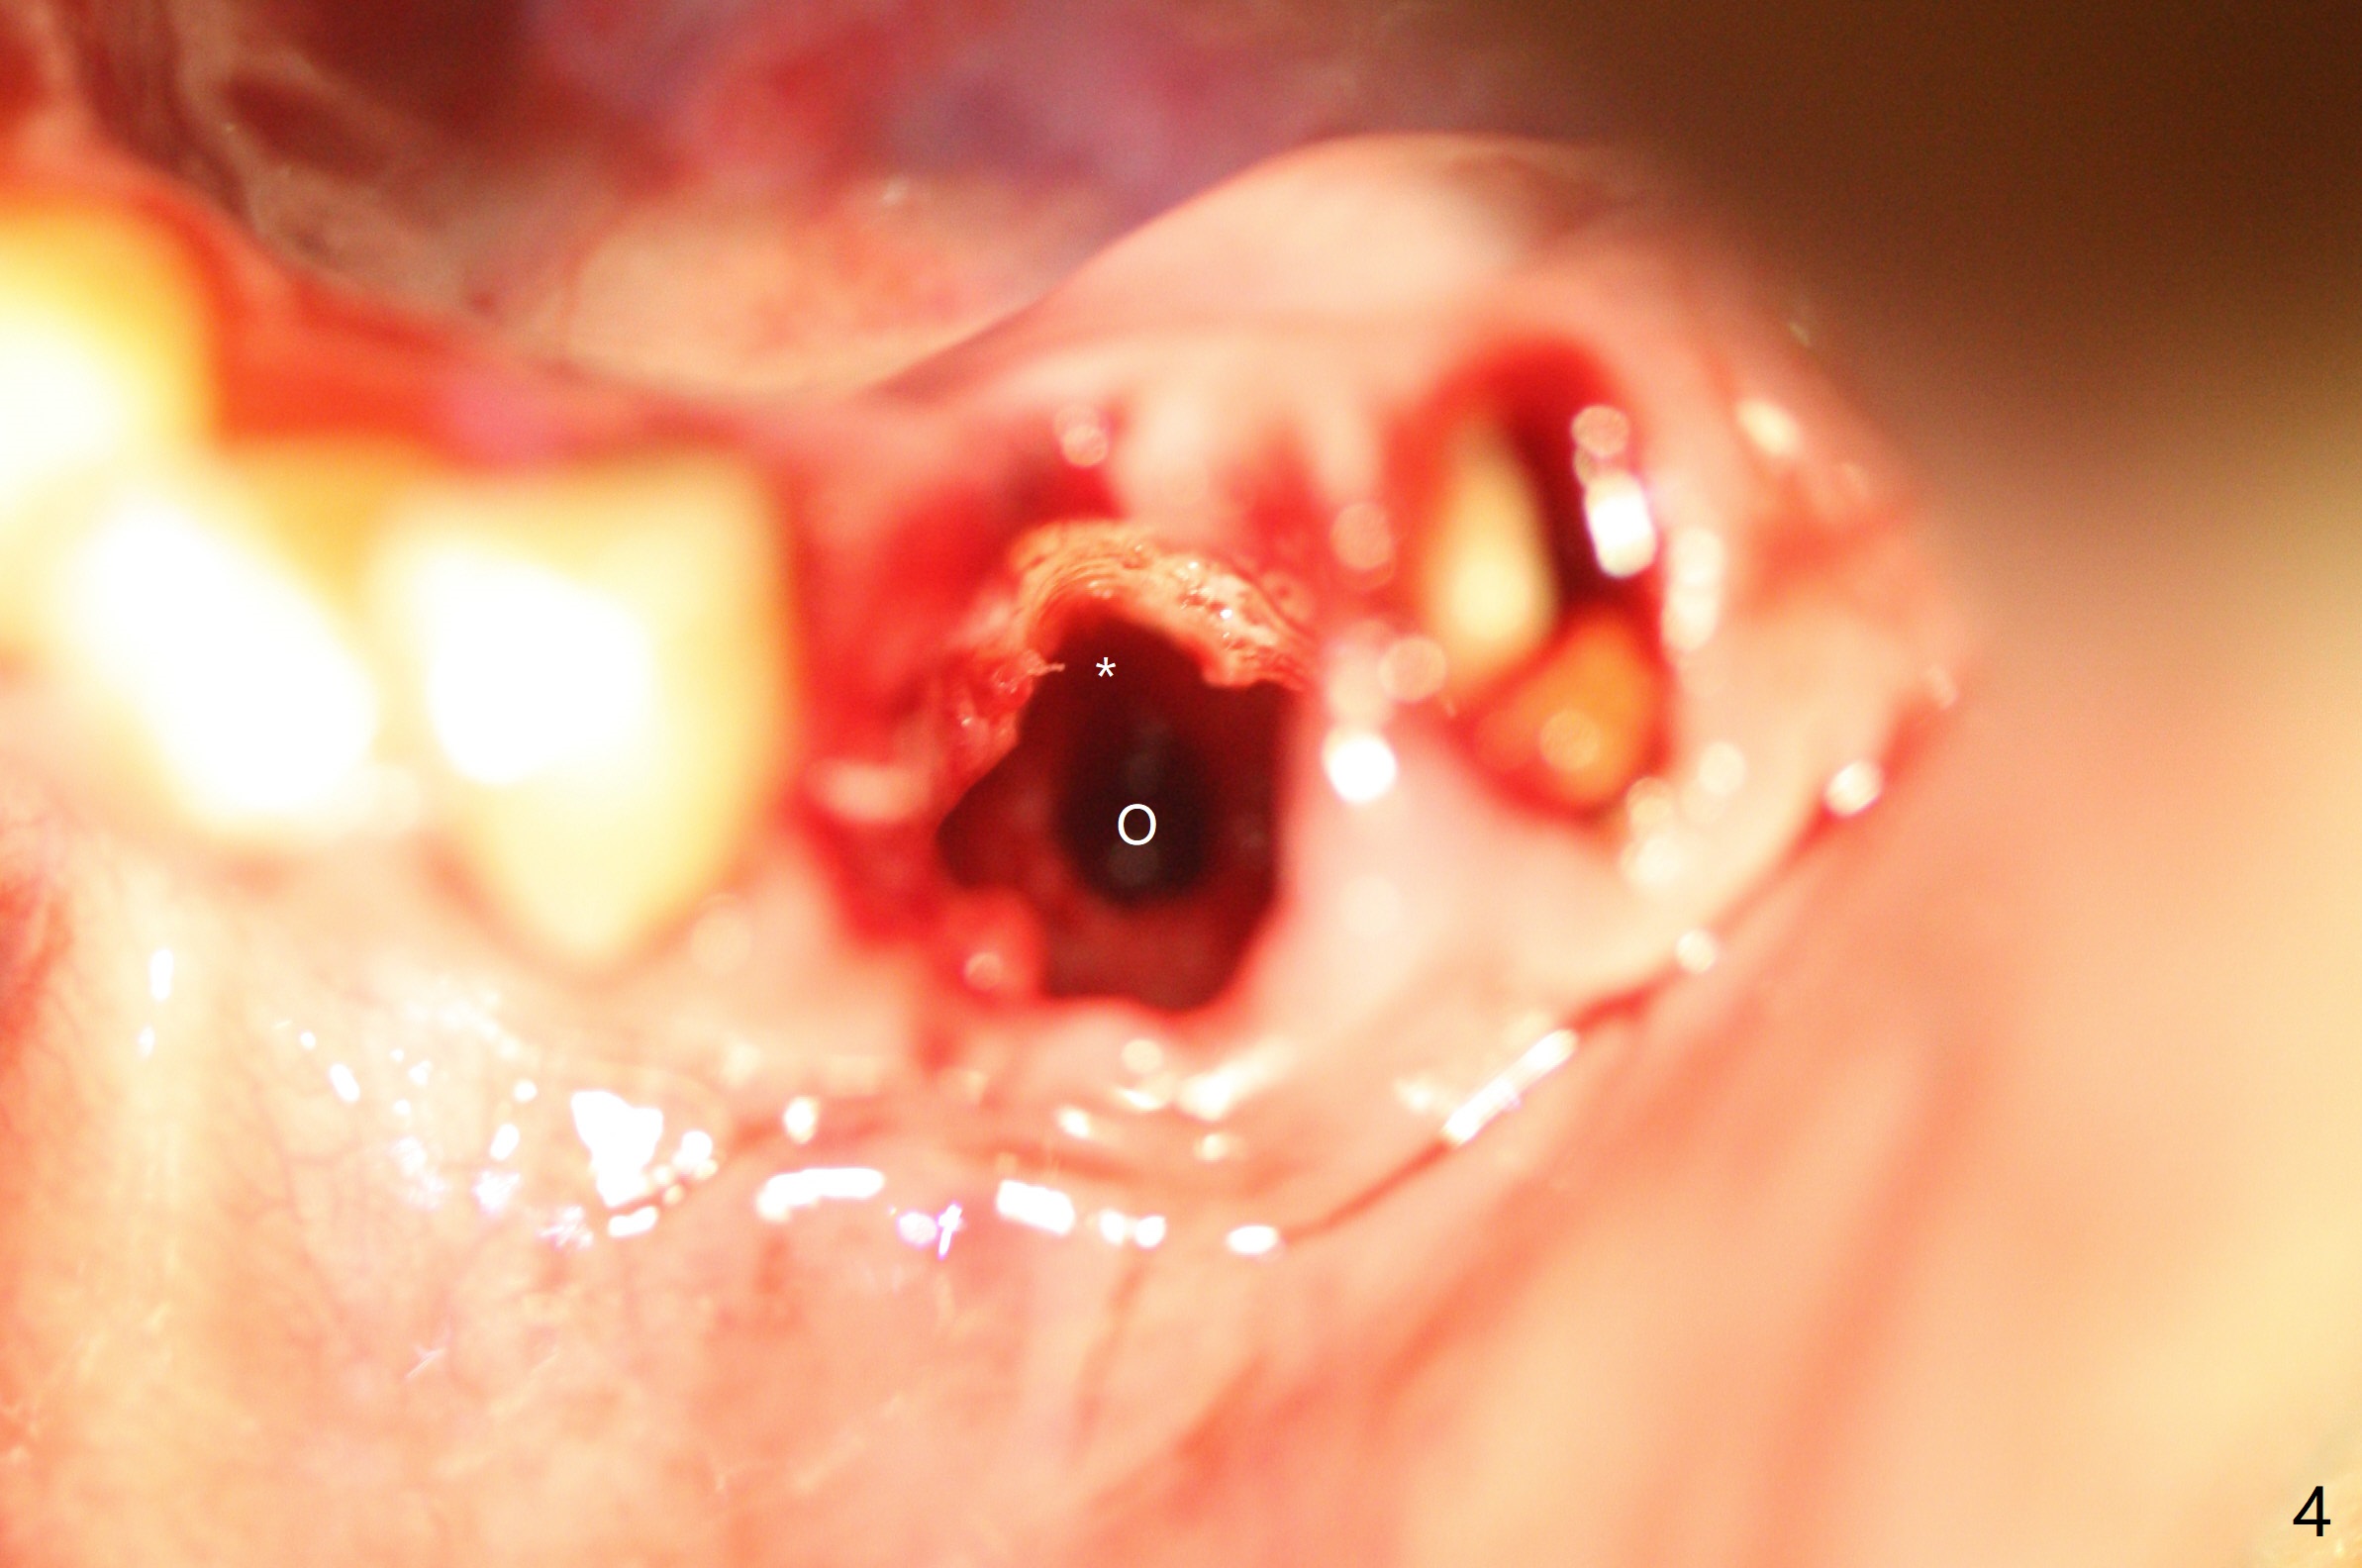

After removal of the split residual roots at #22 (Fig.1), the buccal wall is found to be defective, while the coronal portion of the lingual one (Fig.2 L) is confirmed to be more buccal than the apical portion. A vertical slot is made in the coronal portion of the lingual plate (Fig.3 *) in order to establish osteotomy lingual (Fig.4 O). The depth of the osteotomy in the apical native bone is 4.8 mm (Fig.5 CT coronal section). After the final drill (3 mm) is removed, a 3.8x16 mm implant is placed lingually for secure 2-pointed fixation (Fig.6,7, coronally: mesiolinguodistal; apically: in the native bone (Fig.9)). The essence of the lingual placement is the presence of a large buccal gap for Osteogen plug (Fig.8 yellow) and allograft (Fig.8 red, 9,10 (*)) for potential regeneration of the buccal plate. With bone graft and the overlying provisional (Fig.11 P), the buccal plate seems to have been established (*) 1 week postop. There is no obvious implant thread exposure 8 months postop (Fig.12). But the buccal plate is atrophic when the crown is cemented (~10 months postop, Fig.13).